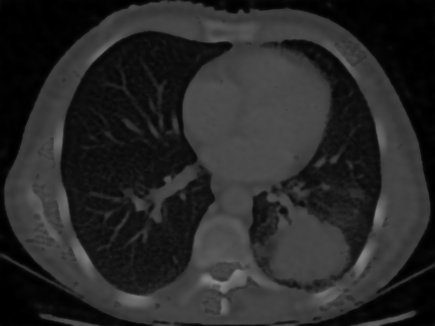

Sparse-View CT Reconstruction

We reconstruct a chest CT from only 100 sparse projections. Optimization with Muon significantly reduces streak artifacts and recovers fine anatomical structures (such as bronchi) compared to Adam.